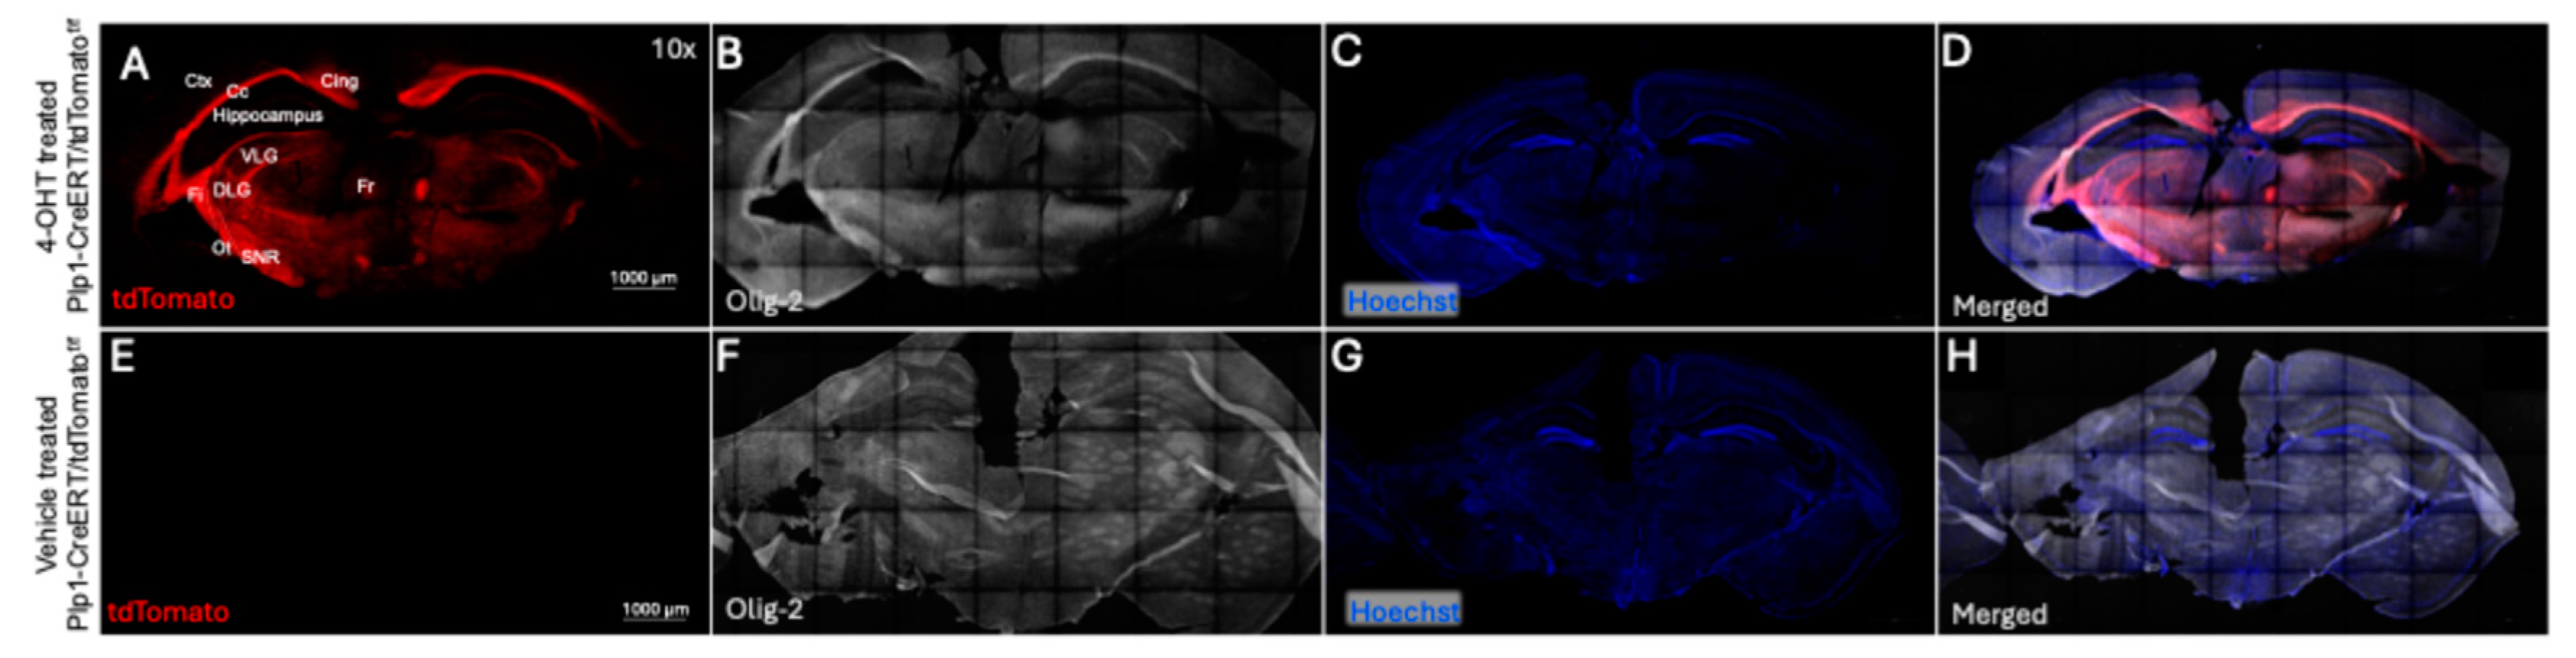

Figure 4.

Coronal plane section of brain of Plp1-CreERT/tdTomatof/f mice. A-D. Immunofluorescence of coronal brain sections of 4-OHT treated mouse showing the CreERT mediated tdTomato expression (red, A) and Olig 2 stain (white, B), and Hoechst (blue, C), and merged images (D) in different regions of brain including hippocampus, cortex and optic tract. E-H. vehicle treated mouse brain not showing tdTomato expression (no visible red, E) and Olig 2 stain (white, F), Hoechst (G), and merged images (H). Annotation in A is as follows; (Ctx) Cerebral cortex, (Cg) Cingulum, (Fr) Fasciculus retroflexus, (Fi) fimbria, (Cc) Corpus callosum, (Ot) Optic tract, (VLG) Ventral lateral geniculus, (DLG) Dorsal lateral geniculus, (SNR) Substantia nigra. Scale bar is 1000 µM. N=2 for 4-OHT treated and N=1 for vehicle treated mouse.

Figure 4). Although unexpected, and in some circumstances a potential issue, this broad distribution of CreERT activation raises the possibility of using this method to study gene KO not only in the visual pathway but also in certain brain regions involved in visual processing.